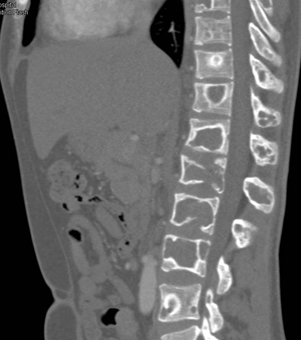

The best dx in this case is?

renal osteodystrophy

fibrous dysplasia

multiple myeloma

myelofibrosis